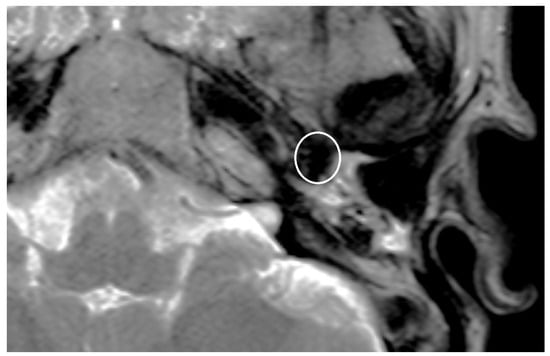

| PORP | 2.0 mm | 3.1 mm | 5.4 mm |

| TORP | 3.6 mm | 4.7 mm | 7.2 mm |

| Mesh | 0.1 mm | 3.6 mm | 5.8 mm |